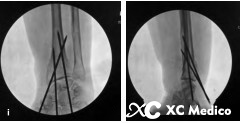

3. Если вход и точки выхода Киршнера очень близки к перелому, может произойти сбой фиксации. Два спинных провода Kirschner не должны проходить через пальмовую кору на том же уровне, а точка выхода из ладони должна находиться в 2 см от места перелома. См. Рисунки AC ниже.

6. В длинных переломах сегмента эпифизарного конца можно использовать большую наклонную проволоку Киршнера. Тем не менее, проволока Киршнера может проскользнуть в медуллярную полость, и его трудно исправить (рисунки AD ниже).